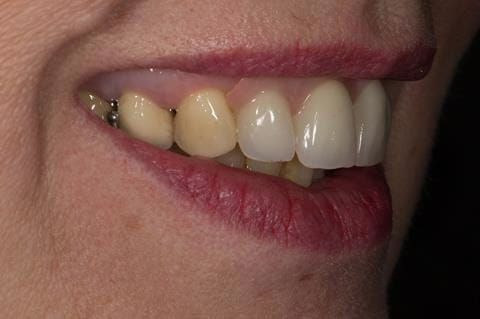

- High smile line showing gum above gingival zeniths of upper front teeth when smiling. Aesthetic failure of the upper four incisors with inflammation of the gingivae and mis-match of the gingival zenith levels.

Following consultation and second discussion appointment the patient chose to have option 3 namely, a maxillary cobalt chromium based partial denture/protective occlusal splint. The clinical situation and treatment process is shown in detail below with photographs. The patient was successfully rehabilitated with this and her quality of life considerably improved. The clinical work was provided by Finlay and the technical work by Rowan.